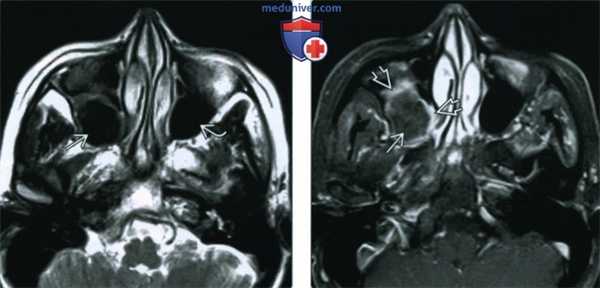

3. МРТ при мицетоме пазух:

• Т1ВИ:

о Материал с вариабельным сигналом в пораженной пазухе

о Гипоинтенсивный (Т1) сигнал, обусловленный отсутствием воды в плотном солидном мицетоматозном образовании

• Т2ВИ:

о Гипоинтенсивный сигнал (макромолекулярный белок) может быть ошибочно принят за газ

• Т1ВИ С+:

о Воспаленная слизистая оболочка может накапливать контраст

(Слева) МРТ Т2ВИ у женщины среднего возраста с жалобами на легкое ощущение распирания в лице: левая верхнечелюстная пазуха пневматизирована обычно, пневматизация верхнечелюстной пазухи справа снижена за счет материала, интенсивность сигнала в котором практически соответствует газу.

(Справа) При аксиальной МРТ Т1ВИ С+ FS определяется сигнал промежуточной интенсивности в правой верхнечелюстной пазухе, подтверждающий отсутствие газа в ней. Материал в пазухе не накапливает контраст, окружающая слизистая оболочка контрастируется в виде «ободка».